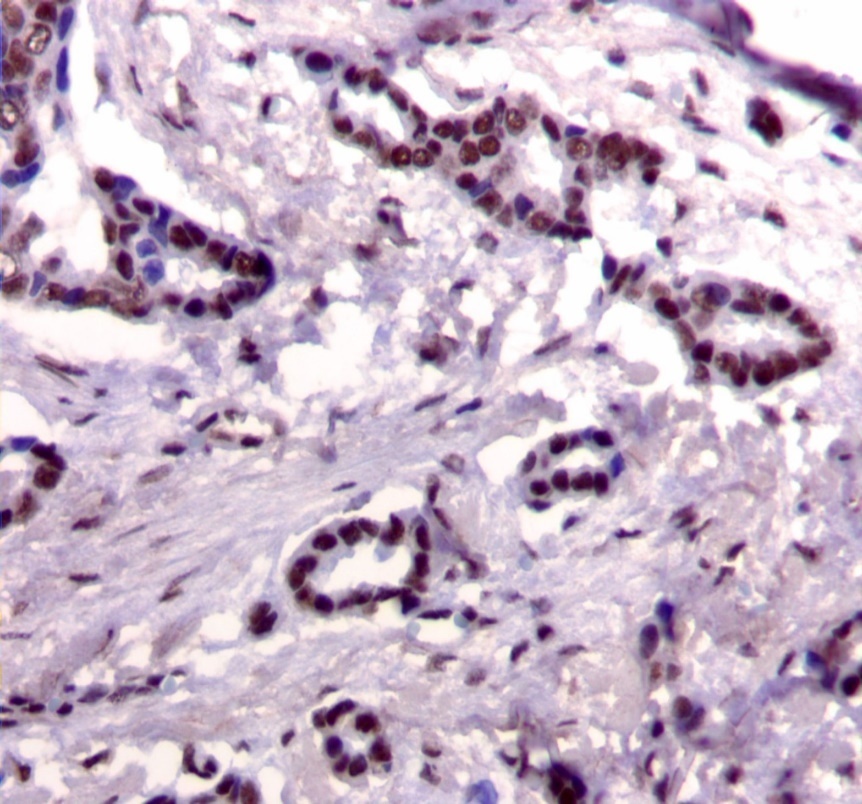

Figure 1.Nuclear staining pattern for IRS-1. (IRS-1 immunohistochemical stain, 200x magnification)

We used the following histologic criteria for IRS-1 and IRS-2 staining patterns which are outlined in a previous study.13 For IRS-1, a nuclear pattern was defined as diffuse nuclear staining (Figure 1). IRS-2 staining patterns were defined using the following criteria: Diffuse cytoplasmic staining was defined as evenly distributed cytoplasmic reactivity (Figure 2); punctate cytoplasmic staining was defined as clearly demarcated puncta of staining within the cytoplasm (Figure 3); and membrane staining was defined as focal or diffuse membranous staining (Figure 4). Sections of normal pancreas and normal breast tissue were used for positive and negative controls. The pathologists assessing staining patterns were blinded to the tumor recurrence score and all other data at the time of assessment.